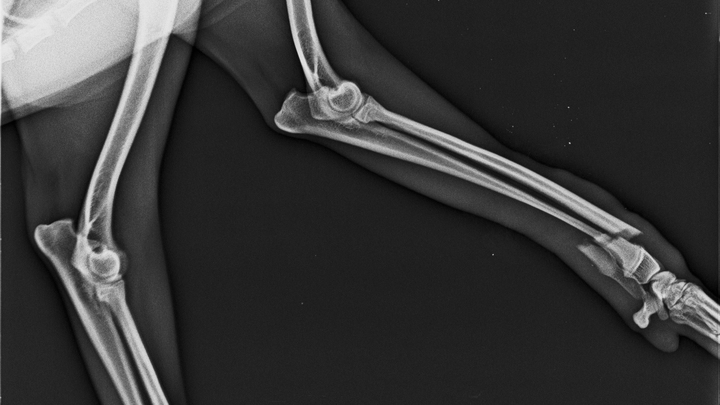

La hemos llevado al veterinario y nos han dado un diagnóstico un tanto complicado el cual es : Fractura Transversa cerrada con desplazamiento de radio y cubito.